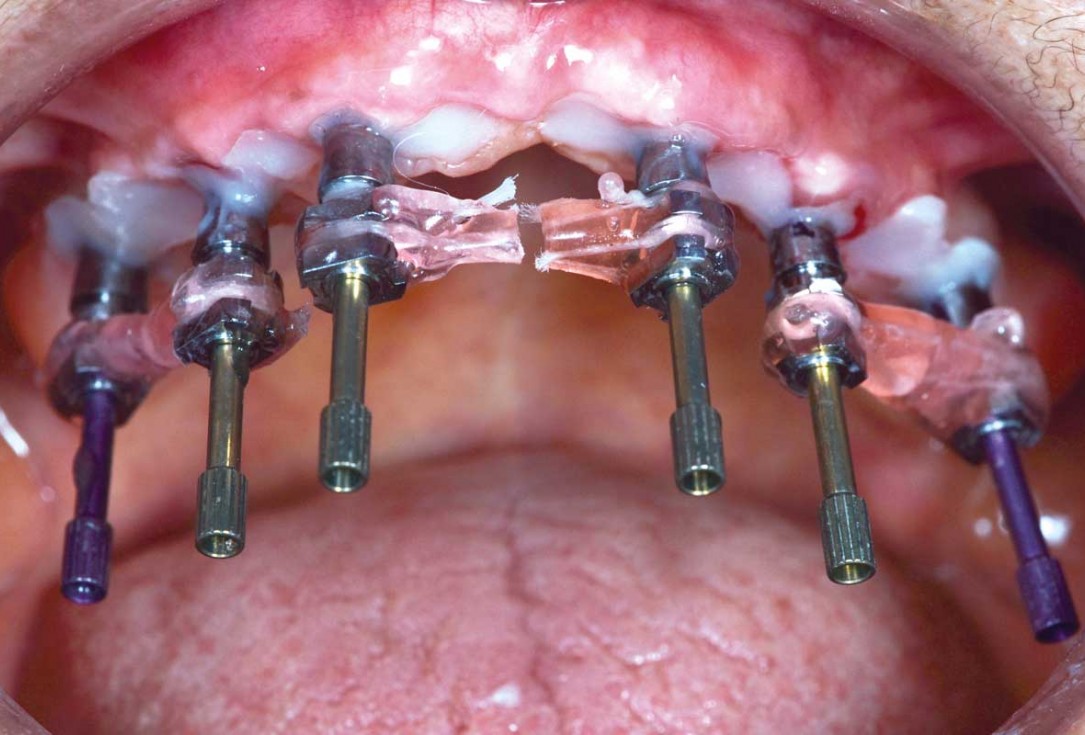

Full arch GBR using cerabone®, maxgraft® and Jason® membrane with simultaneous implantation of 6 Straumann® implants - Dres. A. Signorio and G. Molina